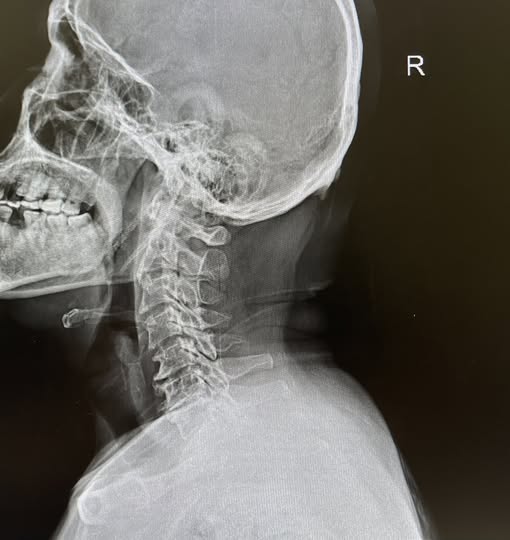

“ปวดแบบไหนครับ?” ผมถาม “ปวดเริ่มจากท้ายทอยค่ะหมอ แล้วมันวิ่งจี๊ดขึ้นมาข้ามหัว มาตุบๆ ที่เบ้าตาขวา บางทีก็ปวดขมับด้วยค่ะ” ประโยคนี้แหละครับ คือ “กุญแจสำคัญ” ไมเกรนแท้ๆ มักจะไม่เริ่มจากท้ายทอยแบบชัดเจนขนาดนี้… พอหมอลองกดจุดที่ “ข้อต่อกระดูกคอข้อที่ 2” ของคุณแอน เธอก็ร้องโอ๊ย แล้วบอกว่า “ใช่เลยหมอ! มันร้าวไปที่ตาเลย!”

สรุปเคสนี้ไม่ใช่ไมเกรนครับ แต่เป็น “คอเสื่อมจากการก้มทำงาน” พอรักษาที่คอ อาการปวดหัวที่เบ้าตาก็หายไปเองโดยไม่ต้องกินยาไมเกรนอีกเลย ทำไม “คอ” ถึงทำให้ “ปวดหัว” ได้? งงไหมครับ? คออยู่ข้างล่าง แต่ทำไมไปปวดที่หัวหรือกระบอกตา?

สาเหตุก็เพราะ “เส้นประสาทมันคุยกัน” ครับ เส้นประสาทที่รับความรู้สึกจาก “คอส่วนบน” (C1-C3) มันส่งสัญญาณเข้าไปที่ก้านสมอง ซึ่งดันไปเป็นจุดเดียวกับที่รับสัญญาณจาก “ใบหน้าและศีรษะ” (Trigeminal nerve) พอกระดูกคอเสื่อม หรือกล้ามเนื้อคอเกร็งมากๆ มันส่งสัญญาณเจ็บปวดไปที่ก้านสมอง… สมองเกิดความสับสนครับ นึกว่าความเจ็บนั้นมาจาก “หัว” หรือ “ตา” ก็เลยแปลผลออกมาเป็นอาการปวดหัวตุบๆ นั่นเอง